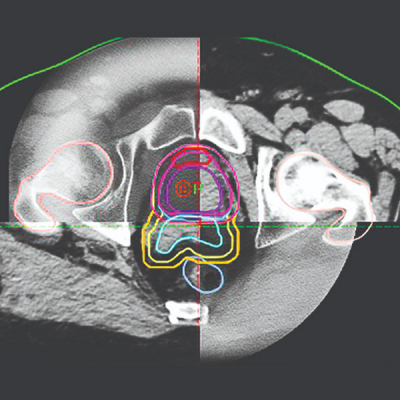

Las imágenes de referencia son las utilizadas para delinear los volúmenes de tratamiento y los órganos de riesgo en el proceso de la planificación de la radioterapia como se realiza en la radioterapia conformada en tres dimensiones. Existe una íntima conexión entre los procesos de obtención de imágenes de referencia y las imágenes obtenidas durante la sesión de radioterapia, ya que IGRT se basa directamente en las modalidades de obtención de imágenes de la planificación como coordenadas de referencia para localizar el volumen de tratamiento en el paciente. La variedad de tecnologías de imágenes médicas utilizadas en la planificación incluye tomografía axial computarizada (TAC) de rayos X , imágenes por resonancia magnética nuclear (RMN) y tomografía por emisión de positrones (PET), entre otras.

El paciente se coloca en la mesa de tratamiento en la misma posición que se planificó a partir del conjunto de datos de imágenes de referencia. Un ejemplo de IGRT incluiría la adquisición de un conjunto de datos de tomografía computarizada de haz cónico (CBCT) antes de la sesión de radioterapia y compararla con el conjunto de datos de planificación de tomografía computarizada (TAC) de la planificación. La IGRT también incluye radiografías planas de kilovoltaje (kV) o imágenes de megavoltaje (MV) obtenidas en la sesión de radioterapia y compararlas con radiografías digitales reconstruidas (DRR) de la TAC de planificación. Estos dos métodos comprenden la mayor parte de las estrategias de IGRT empleadas alrededor de 2013. Gracias a los avances en la tecnología de imágenes, combinados con una mayor comprensión de la biología humana y tumoral a nivel molecular, el impacto de IGRT en el tratamiento con radioterapia continúa evolucionando.

Tomografía computarizada de haz cónico

Los sistemas guiados por imágenes basados en tomografía computarizada de haz cónico (CBCT, Cone-beam computed tomography) se han integrado con aceleradores lineales médicos con gran éxito. Con las mejoras en la tecnología de pantalla plana, CBCT ha podido proporcionar imágenes volumétricas y permite la monitorización radiográfica o fluoroscópica durante todo el proceso de tratamiento. La TC de haz cónico adquiere muchas proyecciones sobre todo el volumen de interés en cada proyección. Utilizando estrategias de reconstrucción impulsadas por Feldkamp, las proyecciones 2D se reconstruyen en un volumen 3D análogo al conjunto de datos de planificación de TC.